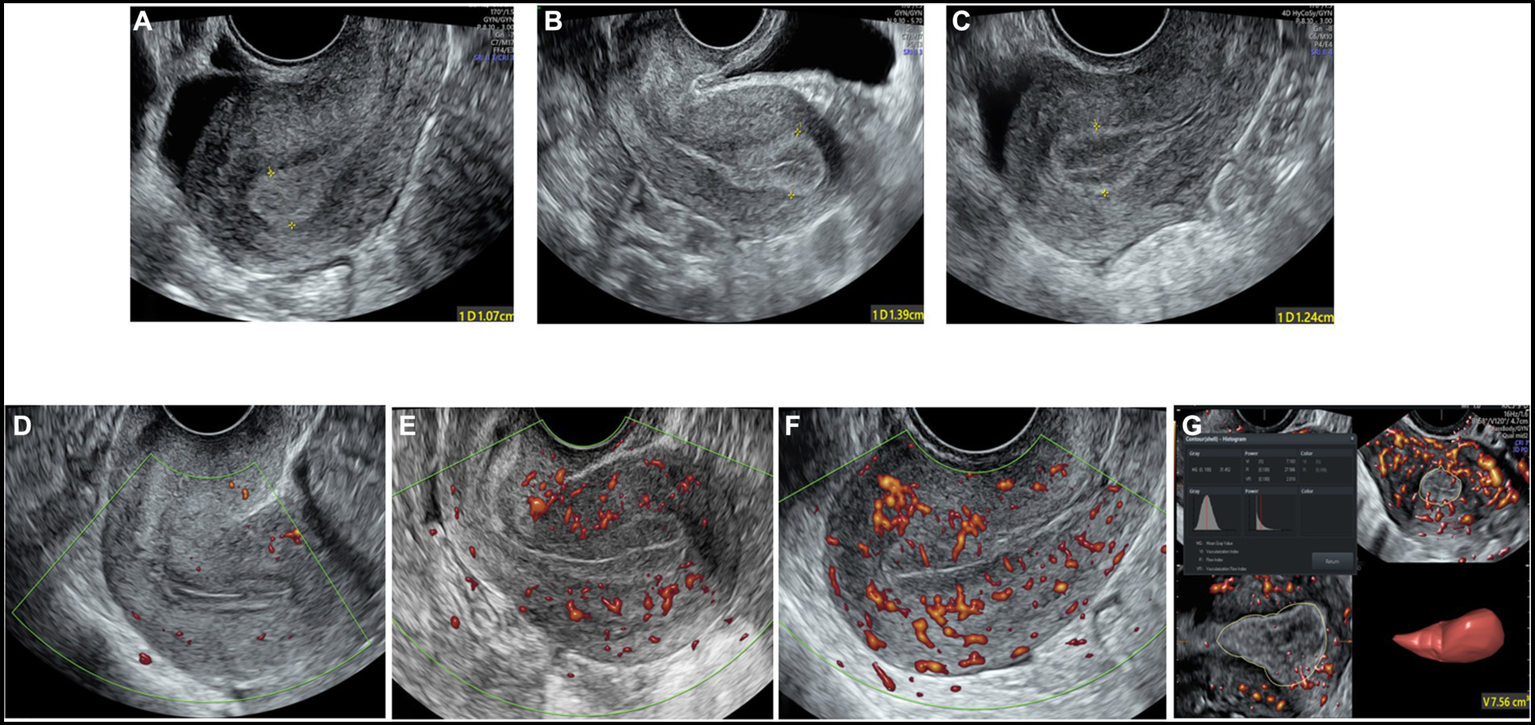

The maximum diameter of the endometrium was measured in the longitudinal plane. The Gonen classification criteria (27), in which the endometrial pattern is determined by comparing the echo of the endometrium to that of the adjacent myometrium, were adopted to evaluate endometrial morphology as follows: Type A: an entirely homogeneous, hyperechogenic endometrium with increased reflectivity and no visualized central echogenic lines; Type B: an endometrium with the same reflectivity as the surrounding myometrium, with a nonprominent or absent central echogenic line; and Type C: a “triple-line” endometrium, consisting of prominent outer and central hyperechogenic lines and inner hypoechogenic or black regions (Figures 2A–C).

Figure 2

The two-dimensional grayscale image shows the endometrial morphology. (A) Type A endometrial pattern; (B) type B endometrial pattern; (C) type C endometrial pattern. Power Doppler shows the blood flow pattern of the endometrium. (D) Blood flow pattern I; (E) blood flow pattern II; (F) blood flow pattern III. (G) Three-dimensional image showing the vascularization parameters and endometrial volume.

Blood flow distribution was observed in the longitudinal plane of the uterus. Endometrial blood perfusion was classified as follows based on the Applebaum classification standard (20): I: blood vessels pass through the outer hypoechoic area and surround the endometrium but do not enter the hyperechoic endometrial margin; II: blood vessels penetrate the hyperechogenic outer margin of the endometrium but do not enter the hypoechogenic inner area; and III: blood vessels enter the hypoechoic intraendometrial area (Figures 2D–F).